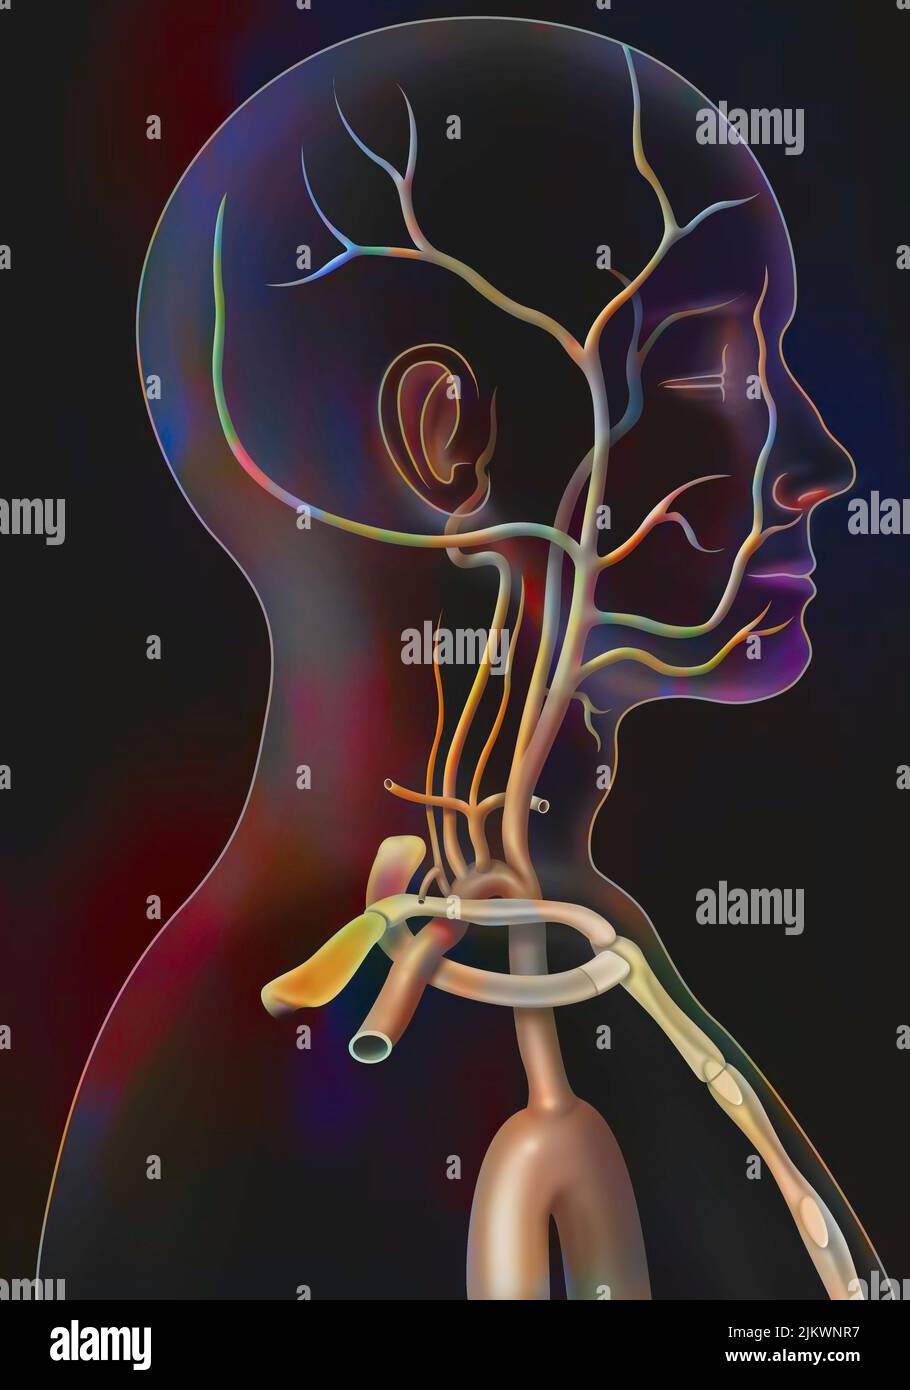

RMJE9NWM–Dieses anatomische Bild zeigt die Arterien unter dem Gehirn, einem wichtigen Teil des menschlichen Kreislaufsystems. Die Arterien sind dafür verantwortlich, das Gehirn mit Blut zu versorgen und seine Funktion zu gewährleisten. Die Nahansicht hilft beim Verständnis ihrer Struktur und Rolle für die Gesundheit und Funktion des Gehirns.

RM2JYR3FK–Thomas Willis war ein berühmter englischer Arzt und Anatom aus dem 17. Jahrhundert, der vor allem für seine Arbeit über das Gehirn und das Nervensystem bekannt war. Er trug maßgeblich zum Verständnis des Kreislaufsystems bei, einschließlich der Beschreibung des Kreises von Willis, einem kritischen Bereich der Blutversorgung des Gehirns. Willis’ Arbeit legte Grundprinzipien in der Neuroanatomie und Physiologie.